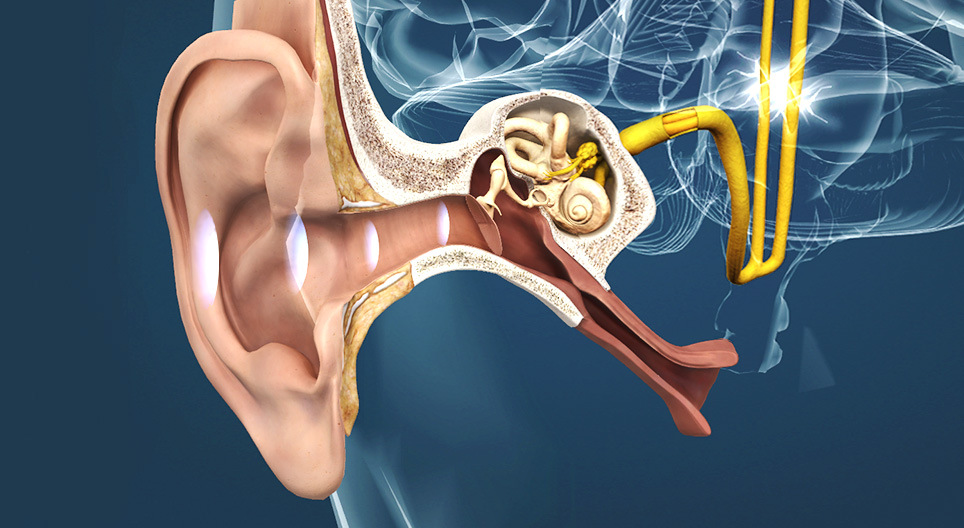

- ušní boltec - Zvukové vlny převádí do vnějšího zvukovodu. Skládá se především z chrupavky.

- vnější zvukovod - Zvukové vlny převádí k bubínku. Výstelka zvukovodu obsahuje mazove žlázy, které produkujú ušní maz, který ji chrání před poraněními a infekcemi. Nadměrný ušní maz může bránit průchodu zvuku do zvukovodu, což způsobuje dočasnou ztrátu sluchu.

- střední ucho - Začíná bubínkem, na němž jsou napojeny tři sluchové kůstky. S hltanem ho propojuje Eustachova trubice.

- vnitřní ucho - Má důležitou roli při rovnováze a slyšení.

- sluchový nerv - VIII. hlavový nerv, nesoucí signály z hlemýždě vnitřního ucha do mozku. Tento nerv také nese informaci zodpovědnou za vnímání rovnováhy, a proto je také nazýván sluchově rovnovážný nerv.

- sluchová dráha - Je pokračováním sluchového nervu do mozku. Jeho axony přenášejí podnět do sluchového centra přes thalamus.

- sluchové centrum - Korové centrum, které se nachází ve spánkovém laloku, zpracovává zvuk. Jeho jednotlivé oblasti se aktivují v závislosti na výšce zvuku.

- Eustachova trubice - Spojuje nosní dutiny se středním uchem (bubínkové dutiny). Přes ni se vyrovnává tlak mezi středním uchem a vnějším světem. Obvykle se otevře při polykání. Když je trvale uzavřena, tlak vzduchu ve středním uchu klesá, proto sa ucho "zablokuje". Když se vnější tlak vzduchu mění můžeme slyšet praskavé zvuky. Eustachova trubice se otevře a vzduch proudí z bubínkové dutiny (v případě, že vnější tlak vzduchu je nižší) nebo do ní (v případě, že vnější tlak vzduchu je vyšší).

- ušní boltec - Zvukové vlny převádí do vnějšího zvukovodu. Skládá se především z chrupavky.

- vnější zvukovod - Zvukové vlny převádí k bubínku. Výstelka zvukovodu obsahuje mazove žlázy, které produkujú ušní maz, který ji chrání před poraněními a infekcemi. Nadměrný ušní maz může bránit průchodu zvuku do zvukovodu, což způsobuje dočasnou ztrátu sluchu.

- střední ucho - Začíná bubínkem, na němž jsou napojeny tři sluchové kůstky. S hltanem ho propojuje Eustachova trubice.

- vnitřní ucho - Má důležitou roli při rovnováze a slyšení.

- sluchový nerv - VIII. hlavový nerv, nesoucí signály z hlemýždě vnitřního ucha do mozku. Tento nerv také nese informaci zodpovědnou za vnímání rovnováhy, a proto je také nazýván sluchově rovnovážný nerv.

- sluchová dráha - Je pokračováním sluchového nervu do mozku. Jeho axony přenášejí podnět do sluchového centra přes thalamus.

- sluchové centrum - Korové centrum, které se nachází ve spánkovém laloku, zpracovává zvuk. Jeho jednotlivé oblasti se aktivují v závislosti na výšce zvuku.

- Eustachova trubice - Spojuje nosní dutiny se středním uchem (bubínkové dutiny). Přes ni se vyrovnává tlak mezi středním uchem a vnějším světem. Obvykle se otevře při polykání. Když je trvale uzavřena, tlak vzduchu ve středním uchu klesá, proto sa ucho "zablokuje". Když se vnější tlak vzduchu mění můžeme slyšet praskavé zvuky. Eustachova trubice se otevře a vzduch proudí z bubínkové dutiny (v případě, že vnější tlak vzduchu je nižší) nebo do ní (v případě, že vnější tlak vzduchu je vyšší).

Zvuk je vibrací vzduchu, vnímáme ho ušima. Zdravé uši mohou vnímat zvukové vlny s frekvencí od 20 do 20 000 Hz. Stárnutím nebo vystavováním se neustálému hluku se škála frekvence zužuje.

Zvukové vlny vytvářejí signály ve vnitřním uchu, které jsou přenášeny sluchovým nervem a sluchovými drahami do sluchového centra mozkové kůry. Sluchový vjem se vytváří v mozkové kůře.

Zvukové vlny zachycuje ušní boltec a vede je do vnějšího zvukovodu. Zvuk rozvibruje bubínek, který uzavírá zvukovod.

Vibrace bubínku se přenášejí k hlemýždi pomocí kůstek, kladívka, kovadlinky a třmínku.